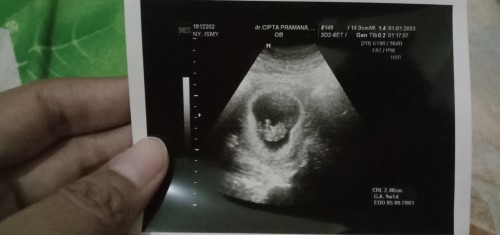

Dulu di usia 7w saya keluar flek darah trs disuruh usg hasilnya belum ada janin masih kantong, terus dokter bilang 2 minggu suruh balik lagi, kalo masih belum ada janin brti BO dan bakal dikasih rujukan ke RS. Sedih, pikiran, campur aduk. Akhirnya pas 18 des 20 saya usg lagi di usia 9w5d cuma ganti dokter karena masih takut aja sama kata2nya, tapi alhamdulillah bahagia banget pas usg liat ada janinnya, djj jg udah ada dan sehat sesuai hpht jg usianya. Gak berhenti bersyukur sampai sekarang ❤️❤️❤️ #firstbaby #pregnancy